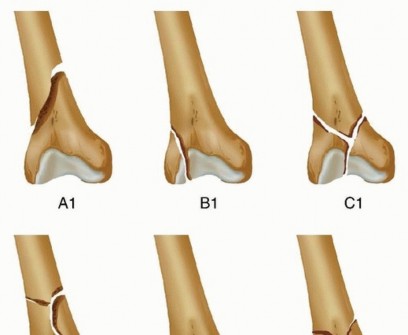

### FIG 7 • AP (A) and lateral (B) views of a three-dimensional (3-D) CT reconstruction of the patient in FIG 3B with a distal femur fracture. The fracture is well defined. C. An oblique 3-D CT reconstruction view showing the same patient and the rotational malalignment between condyles. ## SURGICAL MANAGEMENT 471 The goal of any treatment, nonoperative or operative, is to maintain or restore the congruity of the articular surface and restore the length and alignment of the femur and, subsequently, the limb. Once surgery is deemed appropriate for the patient and the particular injury, the surgical technique options available are determined by the particular fracture pattern. Distal femur fractures have been classified several ways. The OTA/AO classification is probably the most widely accepted classification system and allows some guidance on which techniques are best ( FIG 8; Table 1). Treatment also must be determined based on factors other than the classification alone. The degree of comminution and injury to both the articular surface and bone The amount of fracture displacement The soft tissue injury Associated injuries, other fractures, and injury to neurovascular structures

### FIG 8 • OTA/AO classification for distal femur fractures (types 33A, B, and C).*

OTA/AO Classification of Femoral Fractures

- Classification Description Type A Extra-articular A1 Simple or two-part fracture A2 Metaphyseal butterfly or wedge fracture A3 Metaphysis is comminuted Type B Partial articular B1 Sagittal plane fracture of the lateral femoral condyle B2 Sagittal plane fracture of the medial femoral condyle B3 Any frontal or coronal plane fracture of the condyle (Hoffa type) Type C Intra-articular C1 Simple articular split and metaphyseal injury (T or Y fracture configuration) C2 Simple articular split with comminuted metaphyseal injury C3 Comminuted articular with varying metaphyseal injury Patient's overall condition and injury to other organ systems. This may affect the timing of surgery or the positioning of the patient. There are several principles for the surgical management of distal femur fractures. The articular surface must be reduced anatomically, which usually requires direct visualization through an open exposure (arthrotomy). Simple intra-articular splits may be treated with closed reduction and percutaneous fixation. The extra-articular injury should be dealt with using indirect reduction techniques as much as possible to maintain a biologic soft tissue envelope. Avoidance of stripping of the tissues, especially on the medial side, is ideal. The surgeon must reestablish the length, rotation, and alignment of the femur and the limb. The soft tissue injury and bone quality may dictate treatment decisions. ## Fixation Choices External fixation A temporary bridging external fixator across the knee joint can be used if temporary stabilization is required before definitive fixation. This is usually the case where definitive open reduction and internal fixation (ORIF) is planned. This could be in cases where the soft tissues prevent immediate fixation. Definitive management with bridging or nonbridging external fixation can be used for nonreconstructible joints, very severe soft tissue injuries, or severe osteopenia. Bridging external fixation can be used when definitive ORIF is problematic in certain patient populations, such as Jehovah's witnesses, where additional blood loss can lead to increased morbidity or mortality. This can be done temporarily until the patient's condition improves or until healing ( FIG 9). Intramedullary nailing This can be performed fairly acutely; temporary bridging external fixation is not necessary. 472